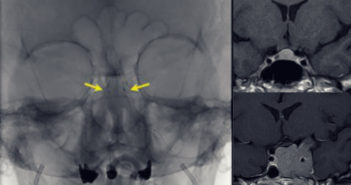

La estimulación cerebral profunda es considerada mundialmente como el tratamiento estándar para algunos pacientes con Parkinson.